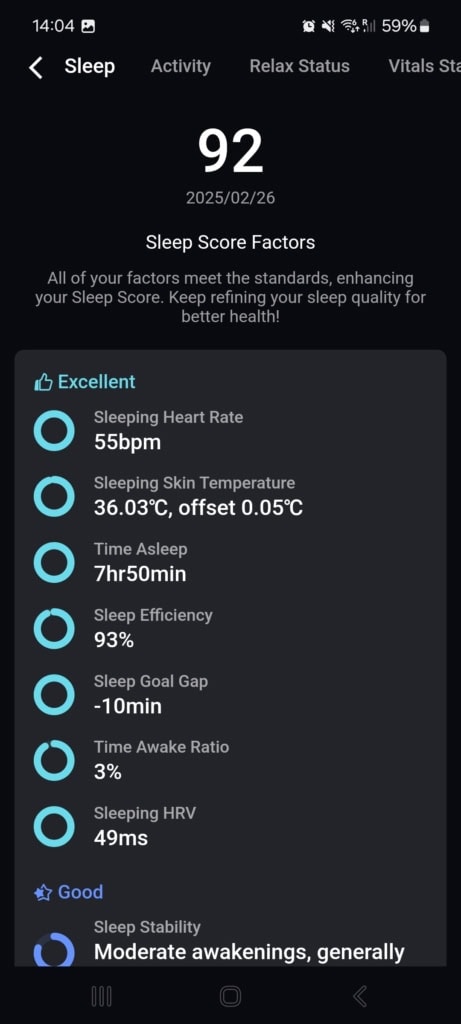

Sen

Aplikacja ustala po każdej nocy wynik snu na podstawie kilku szczegółowych metryk. Podstawą jest całkowity czas snu wyliczony z czasu zaśnięcia i przebudzenia. W tym aspekcie muszę pochwalić pierścień. Określa on nie tylko czas snu, ale także całkowity czas spędzony w łóżku. Te wartości zazwyczaj odpowiadały rzeczywistości i były porównywalne z konkurencyjnymi inteligentnymi pierścieniami.

Jeśli po prostu położyłem się i zasnąłem, w zapisie była tylko bardzo krótka faza przed snem. Jeśli natomiast przewracałem się przed snem z powodu zbyt wczesnego położenia się do łóżka, w analizie znalazłem nawet 50 minut fazy przed snem.

Dobrą dokładność zauważam również w fazie przebudzenia po śnie. W przypadku, gdy po dzwonku budzika od razu wstałem i działałem, ta faza była bardzo krótka. Jeśli natomiast jeszcze chwilę leżałem, faza była odpowiednio długa. Podczas gdy większość inteligentnych pierścieni rejestruje fazę przed snem, faza przebudzenia po śnie często całkowicie brakuje.

Jak wspomniałem wcześniej, pierścień określa długość i udział poszczególnych faz snu. Oprócz czuwania znajdziesz w analizie lekki, głęboki i REM sen.

Oczywiście jest także wynik snu z maksymalną wartością 100, który w większości przypadków zgadzał się z moimi odczuciami w ciągu dnia. Nie brakuje również wykresów i wartości nocnej częstotliwości tętna, zmienności tętna czy nasycenia krwi tlenem. Na koniec warto wspomnieć o pomiarze temperatury i częstotliwości oddechu.

Ogólnie oceniam dokładność i informacje o śnie bardzo pozytywnie. Dane są przejrzyste, a poszczególne metryki są uzupełnione krótkim, bardzo łatwym do zrozumienia komentarzem. Dzięki temu szybko uzyskasz dość szczegółowy wgląd w swój sen, który jest znacznie łatwiejszy do zrozumienia niż obszerne komentarze w niektórych testowanych smart ringach.

Mimo że zalecenia są zazwyczaj adekwatne, mogłyby być miejscami bardziej szczegółowe, zwłaszcza w kontekście faz snu. Kilkakrotnie odkryłem, że mój sen REM lub głęboki jest zbyt krótki, ale nie znalazłem informacji, jak poprawić tę sytuację.